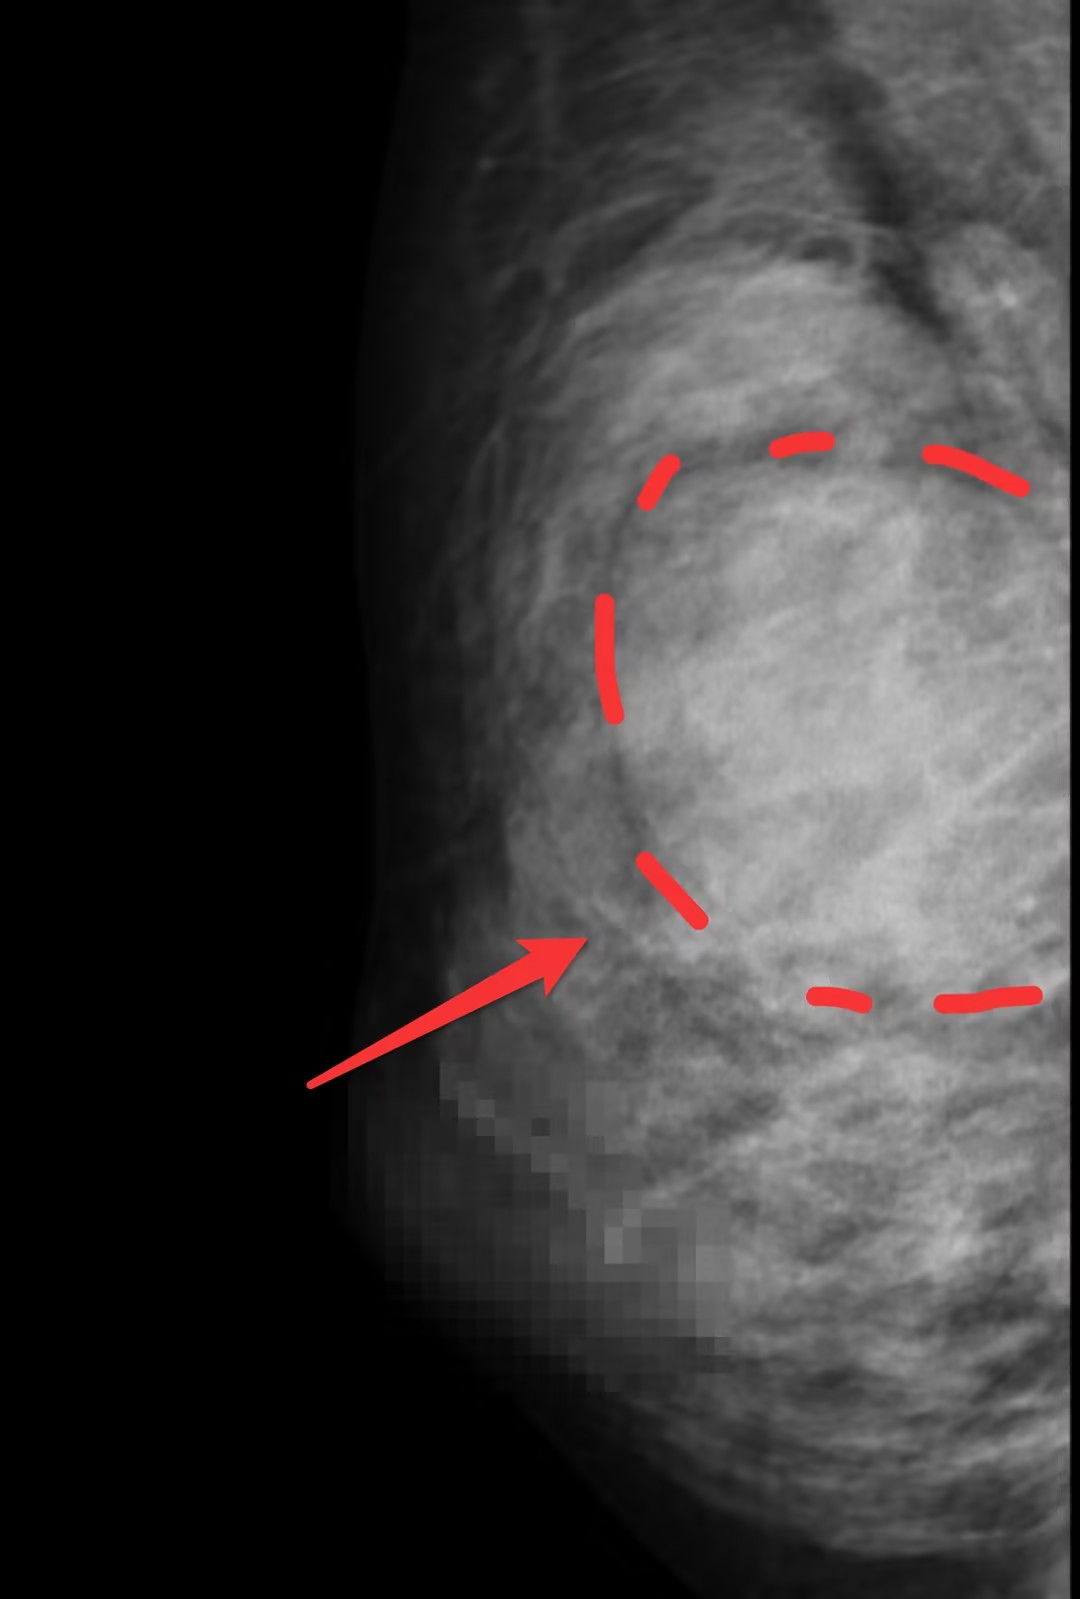

乳腺彩超及钼靶下巨大肿物,完整切除测量约5cm